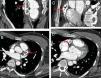

A 29-year-old man was admitted to our emergency department after a cardiac arrest. The patient had suffered sudden cardiac arrest while exercising 30min prior to his medical evaluation. Bystanders on the scene performed cardiopulmonary resuscitation and achieved restoration of spontaneous circulation after about 10min. In the emergency department, the patient developed repeated convulsions. Consequently, the patient received intra-tracheal intubation was admitted to the ICU. A chest computed tomography (CT) showed patchy high-density abnormalities in the heart shadow area (Fig. 1). Electrocardiography and echocardiography results with no obvious abnormalities. The patient's parents reported that he did not have a history of heart surgery. Suspecting cardiogenic etiological factors, we performed a coronary CT angiography (CTA). The results suggested a large mass-associated dilatation of the proximal right coronary artery and left anterior descending coronary artery. Irregular calcification was visible in the lumen of two coronary artery sites with moderate to severe stenosis (Fig. 2). Previous history and the characteristics of coronary CTA suggested Kawasaki disease. After 6 days, the patient was transferred out of the ICU, after which he exhibited a good recovery. The patient was referred to a cardiac specialist and underwent coronary artery bypass grafting a month later.